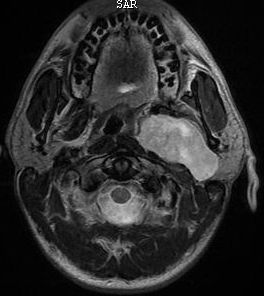

| Schwanom der Carotisloge | 28-jähriger Mann mit einer Raumforderung in der oberen Carotisloge. Schwanom. | ||

![]() |